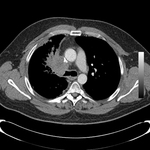

Золотистый-S или обратный S-знак на КТ грудной клетки (изображение слева), отмеченный желтой линией. Гибкая бронхоскопия (изображение справа) показывает центральное обструктивное поражение в левом главном бронхе.

Из коллекций Хосе Фернандо Сантакруза, дипломированного врача, члена Американской коллегии специалистов в области торакальной медицины, DAABIP, и Эрика Фолка, дипломированного врача, магистра наук; используется с разрешения